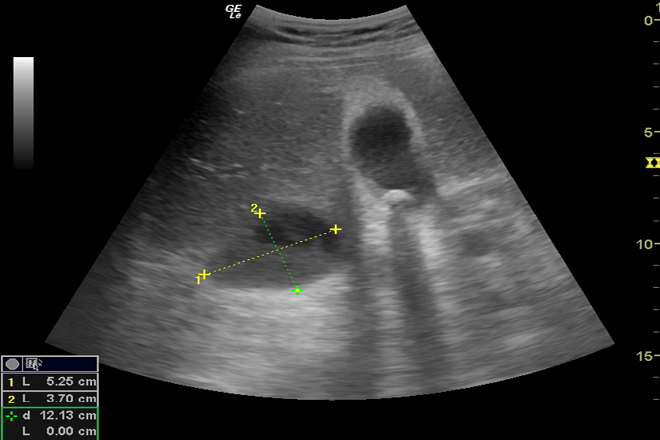

Las imágenes por ultrasonido son una herramienta popular y no invasiva utilizadas con frecuencia en el diagnóstico de las enfermedades del hígado. Un sistema para caracterizar la normalidad grasa y el hígado heterogéneo, utilizando el análisis textural de las  imágenes de ultrasonido de hígado, se propone en este trabajo un enfoque que es capaz de seleccionar las regiones óptimas de interés de las imágenes del hígado. Estas regiones óptimas de intereses se analizan en dos niveles capaces de extraer algunas de las características estadísticas, a saber, la mediana, la desviación estándar. Discriminación entre heterogénea, graso y hígados normales se realiza en un enfoque jerárquico en la etapa de clasificación. Esta etapa, primero, clasifica focal y difusa y luego distingue entre grasa y las normales.

El objetivo de este estudio es desarrollar un método no invasivo basado en el análisis de imágenes de ultrasonido, que no sólo con precisión diagnostique hígados grasos y heterogéneos. Como se mencionó anteriormente, un sistema CAD totalmente automático y eficiente incluye la selección automática de retorno de la inversión, la extracción de características eficientes. El estudio abarca el análisis de 88 sujetos, cuyos hígados dieron,  30 grasos, 39 normales y 19 imágenes del hígado heterogéneos. Las imágenes son de tamaño 560 × 450 píxeles y guardado en formato de mapa de bits. Todas las imágenes se obtuvieron utilizando un B-modo digital Toshiba SSA 550 US sistema de imagen con una sonda convexa y en un tejido 5 MHz armónico de frecuencia de imagen.

En el método propuesto, la imagen del hígado se recorta primero para extraer una amplia región cerca del lóbulo central. La amplia región se divide a 9 bloques vecinos de igual tamaño. La división continúa al siguiente nivel, que  genera 12 bloques formados por la superposición. Las características extraídas de coeficientes WPT son la mediana; la mediana de la imagen muestra el valor numérico de la intensidad de la separación. El valor de la mediana de la intensidad en  imágenes de hígado graso es más alto que la intensidad de los normales debido a su ecogenicidad aumentada causada por la acumulación de grasa.

El algoritmo propuesto para la identificación de hígado graso  es realizado en dos etapas. La primera etapa, de forma automática selecciona algunas regiones de interés una imagen de ultrasonido en el hígado sin necesidad de ninguna ayuda de un experto médico. El WPT se aplica a las regiones de interés seleccionadas como un analizador de textura multi-escala para extraer algunas de las características estadísticas. En la segunda etapa, un jerárquico método de clasificación binario utilizando SVM clasificador es empleado.